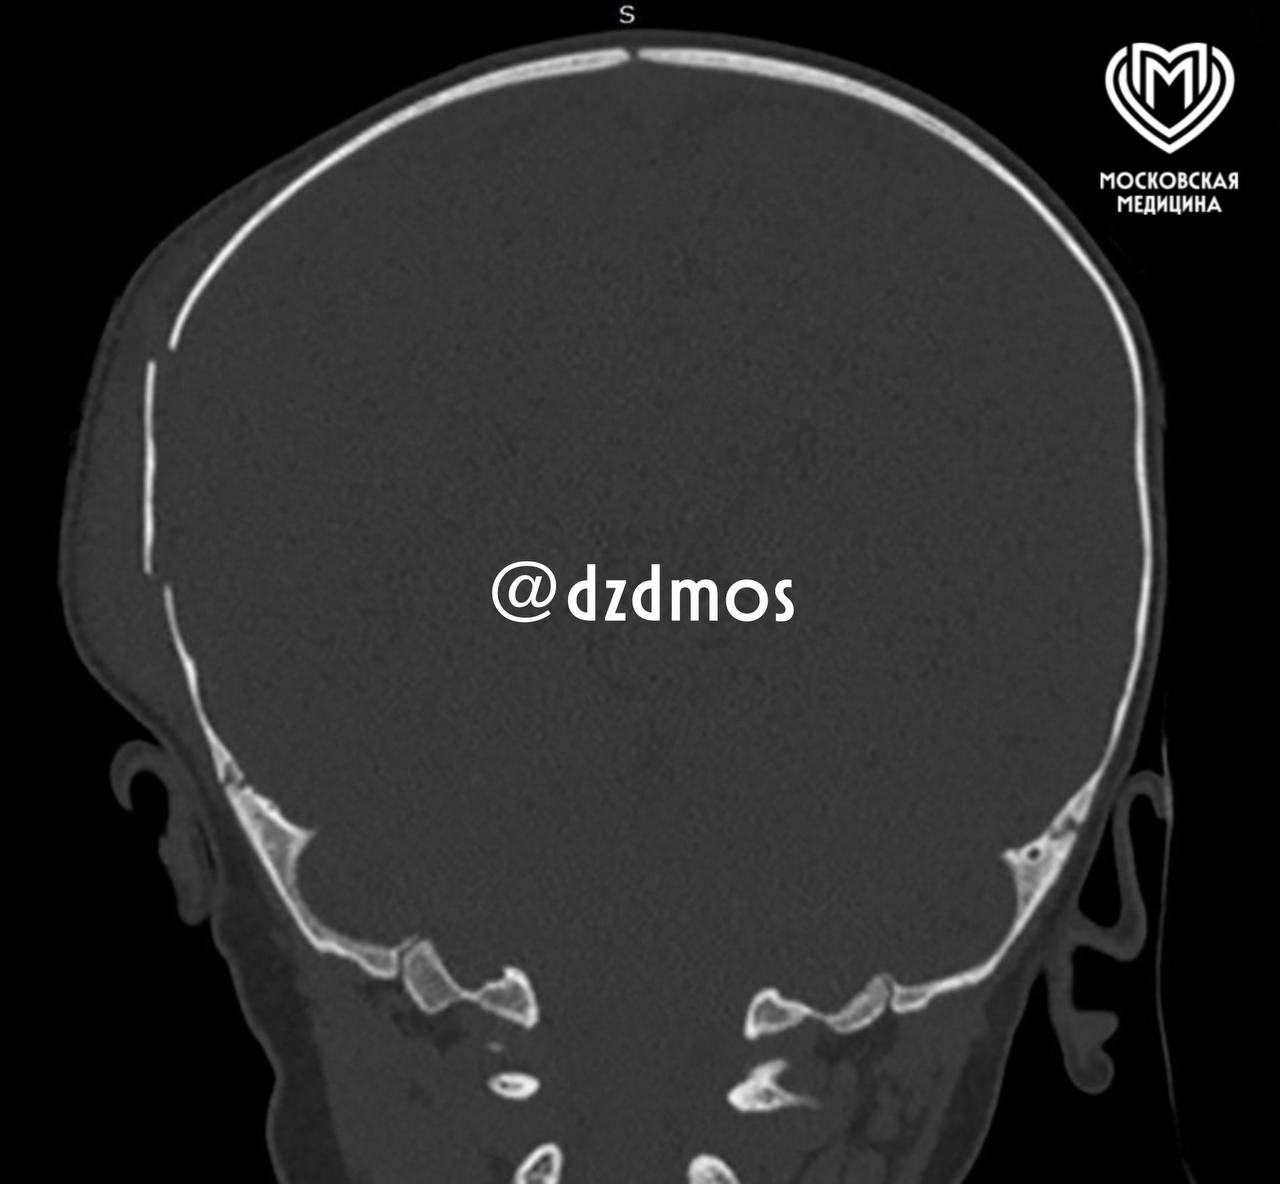

Мать малыша заметила отек на голове, у ребенка началась рвота. Женщина сразу вызвала «скорую». В больнице врачи сделали снимок и увидели серьезную травму — перелом правой теменной кости и гематомы. Нейрохирурги провели срочную операцию и восстановили костные фрагменты.